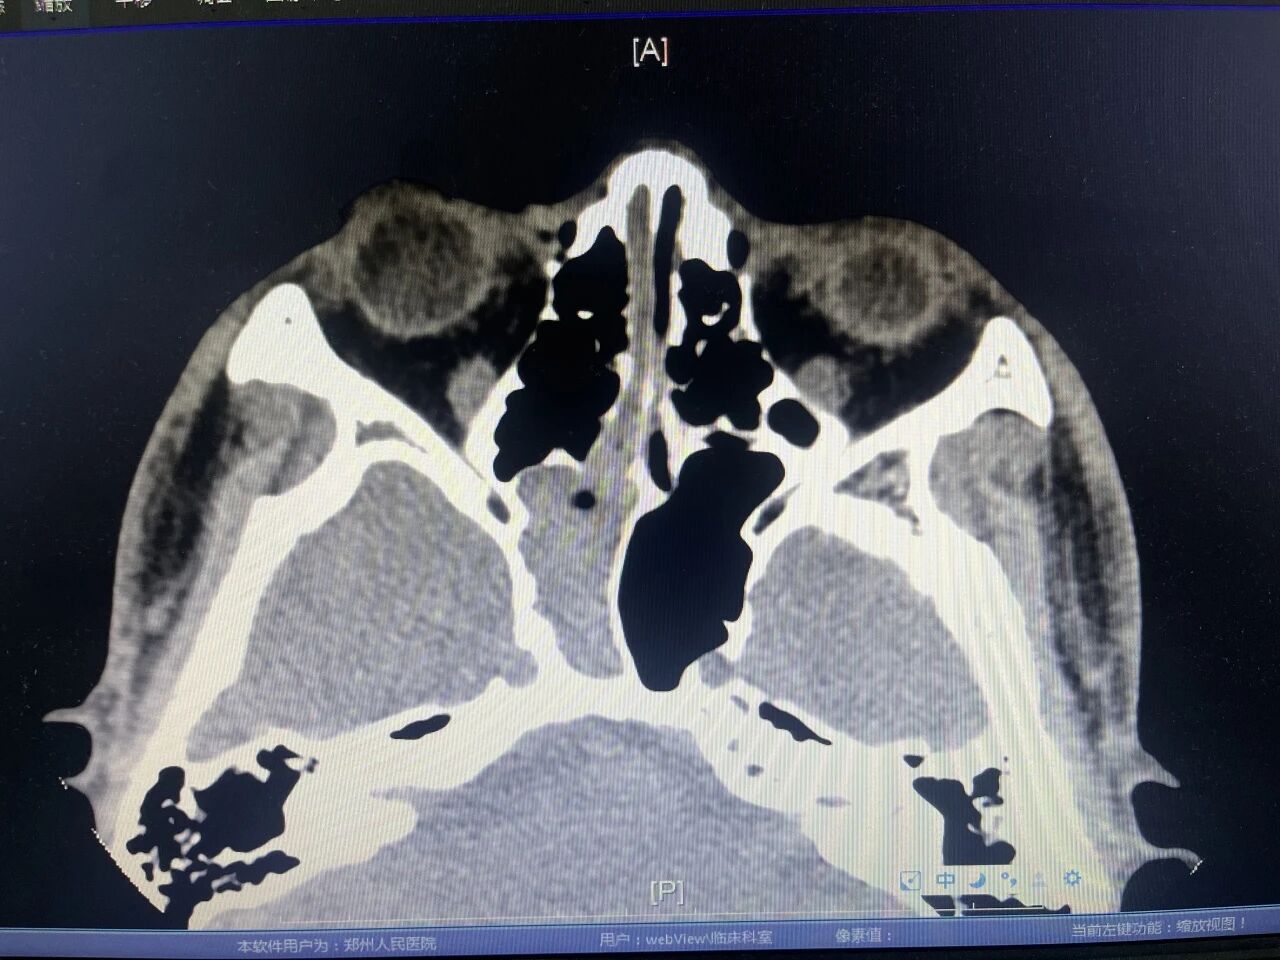

为找到病根,魏晓安排李明进行了鼻窦CT扫描。结果显示,在他鼻腔最深处、位于眼球后方的“蝶窦”内,充满了异常分泌物和新生组织。这层神秘的面纱终于被揭开——李明被确诊为真菌性蝶窦炎。

病因明确后,魏晓主任为李明安排急诊手术。术中清晰可见,李明的蝶窦内充满真菌团块和脓液,正持续不断地“灌注”到鼻中隔。医生彻底清除了蝶窦内的真菌和脓液,成功端掉了“污染源”。术后,李明的鼻塞和肿胀症状迅速缓解,术后第二天便恢复了正常呼吸。